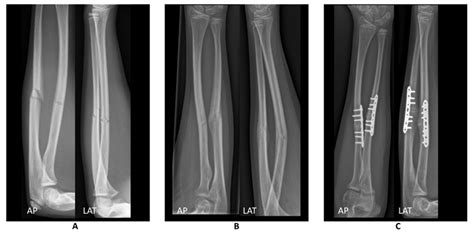

Anteroposterior (AP) View The arm is flat on the table, palm facing up, providing a front-to-back view of the radius and ulna.

Lateral View The arm is turned 90 degrees, showing the side profile of the bones to check for displacement or angling.

• Fractures: Whether the bone is broken completely, partially (a hairline fracture), or fragmented (comminuted fracture).

• Alignment: Checking if the broken ends of the bone are touching or if they have shifted.

• fractured forearm x ray